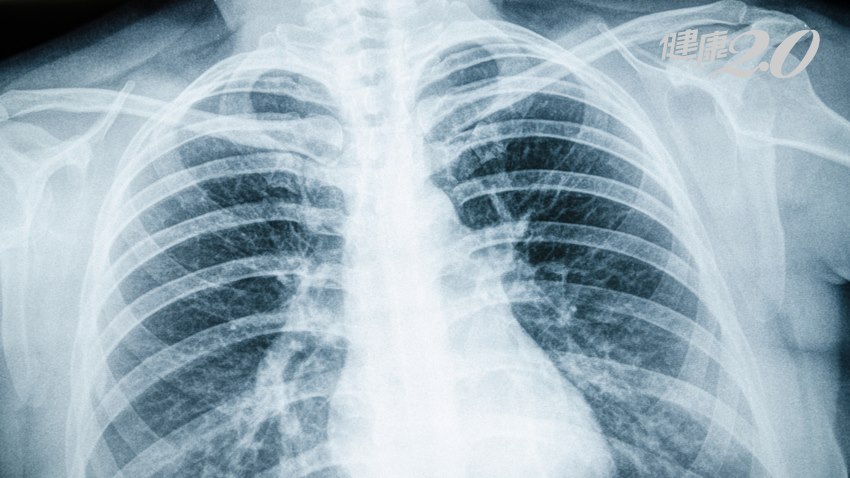

後來是兒女認為不對勁,安排患者做健康檢查,透過肺部低劑量電腦斷層檢查,影像結果看到左右下肺葉,各有明顯的局部肺部纖維化,進一步檢查後,確認是原發性肺纖維化(俗稱菜瓜布肺)。

蔡聰聰解釋,肺纖維化是肺臟受到損傷後,自然出現的結疤現象。如果肺部傷害時間過長或是破壞的面積過大,就會導致肺臟組織硬化並逐漸喪失功能,嚴重會導致病人死亡。抽菸者若患上菜瓜布肺,正是因為菸品中的焦油沉積於肺葉,破壞肺泡,導致肺纖維化。